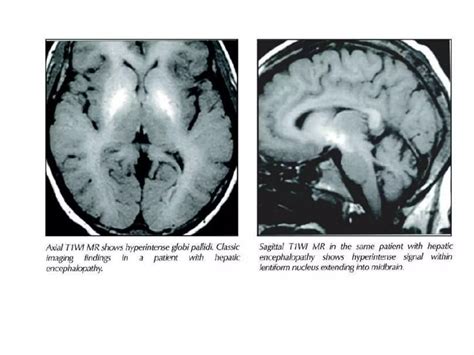

• Organ Failure: Hepatic encephalopathy (liver failure) and uremic encephalopathy (kidney failure) are among the most common causes. In these cases, toxic substances that are usually processed by the liver or kidneys accumulate in the bloodstream and eventually cross the blood-brain barrier.

Because the clinical presentation of Toxic Metabolic Encephalopathy mimics many other conditions—such as primary brain tumors, meningitis, or strokes—the diagnostic process is one of exclusion. Doctors must first rule out structural causes of brain dysfunction using imaging like CT or MRI scans.

• Ammonia Levels: Elevated levels are a strong indicator of hepatic-related encephalopathy.

The outlook for individuals suffering from Toxic Metabolic Encephalopathy depends almost entirely on how quickly the underlying trigger is addressed. In acute, treatable scenarios, patients can often return to their baseline cognitive function with no lasting damage. However, if the metabolic insult is severe or prolonged, there is a risk of secondary damage to the brain, which may manifest as persistent cognitive deficits or structural changes on follow-up imaging.

• toxic metabolic encephalopathy radiology